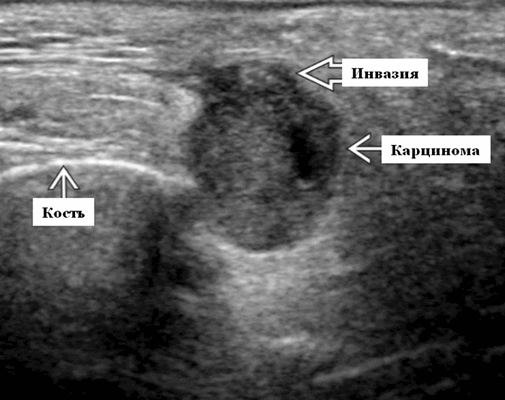

- Опухоли низкой степени злокачественности могут быть четко определены как образования с однородной внутренней архитектурой.

- Опухоли высокой степени злокачественности плохо очерчены с инвазивными краями и неоднородными участками некроза / кровоизлияния.

- ± внежелезистая инвазия мягких тканей, периневральное распространение

Основные диагностические признаки. АКК низкой степени злокачественности выраженная, однородная, гипоэхогенная опухоль. Аденоидно-кистозная карцинома высокой степени злокачественности на ультразвуковом исследовании выглядит как нечеткое, неоднородное, гипоэхогенное образование с внежелезистой инвазией

Серошкальное УЗИ не позволяет отличить АКК от других злокачественных новообразований слюнных желез. Опухоли низкой степени злокачественности могут быть хорошо определены с однородной внутренней архитектурой. Опухоли высокой степени злокачественности плохо определены с инвазивными краями и неоднородными участками некроза / кровоизлияния ± внежелезистая инвазия мягких тканей, периневральное распространение ± диссеминированные метастазы в соседние лимфоузлы